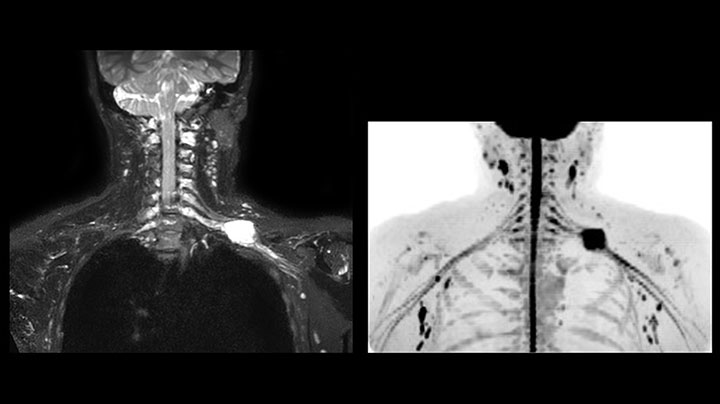

MRI of Pancoast tumor

Although the area between the neck and the top of the lung is one of the most difficult areas for MRI, Prodiva 1.5T images show good quality in this 56-year-old male with Pancoast tumor on the right. mDIXON TFE images shows excellent fat suppression in the neck area and the DWI shows almost no distortion.

Prodiva MRI pancoast tumor DWI, Seirei Mikatahara

Prodiva MRI pancoast tumor mDixon, Seirei Mikatahara

Prodiva MRI pancoast tumor dynamic, Seirei Mikatahara